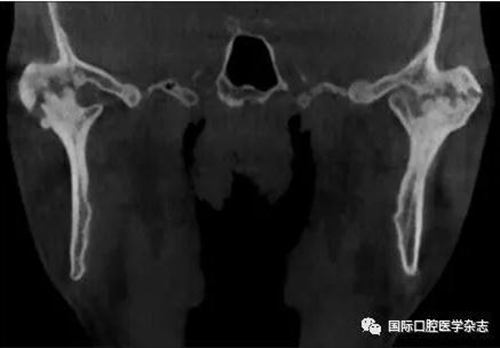

(2)不可復(fù)性關(guān)節(jié)盤前移位(圖1):多見于青壯年,往往與社會心理因素、牙合關(guān)系異常、代謝因素、偏側(cè)咀嚼、夜磨牙及不良習(xí)慣等因素相關(guān)。張口運(yùn)動時,受髁突擠壓變形的關(guān)節(jié)盤不能復(fù)位;臨床有典型的關(guān)節(jié)彈響病史,進(jìn)而彈響消失,出現(xiàn)開口受限,開口時下頜偏患側(cè)及關(guān)節(jié)區(qū)疼痛。測量被動開口度時,開口度不能增大。輔助檢查中,錐形束CT顯示關(guān)節(jié)前間隙增寬,造影片或核磁共振成像(magnetic resonance imaging,MRI)顯示不可復(fù)性關(guān)節(jié)盤前移位。

圖 1 不可復(fù)性關(guān)節(jié)盤前移位